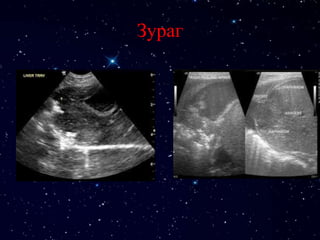

ЭХО

Зураг